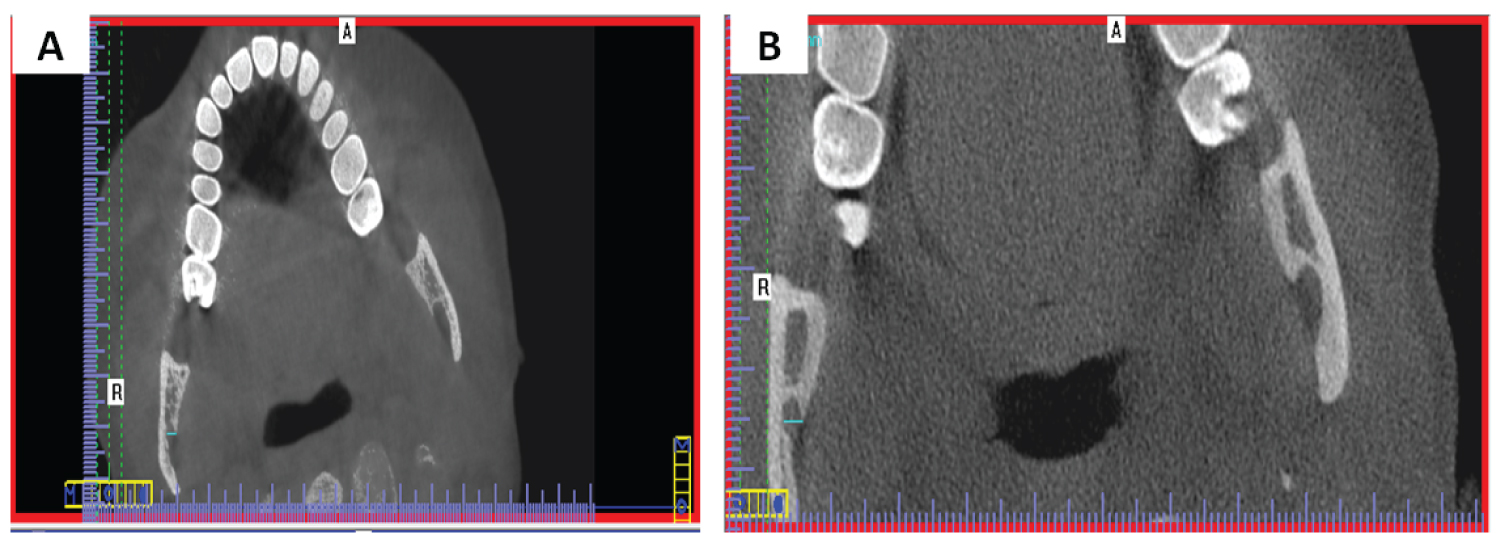

Multi-planar images (MPR) were used to obtain the linear measurements. Standardization was performed on two MPR views and then the measurements were taken on the third plane. The slice thickness was increased to 8 mm to include all structures needed.

To measure distances AB-MF, PB-MF, RW, CW, MN-MF, MF-IB and RH, standardization was done as follows: In the coronal view, the axial plane was scrolled upwards till reaching the axial slice that shows the beginning of complete separation between mandibular condyle and coronoid processes. In the axial view, the view rotated till the condyle and coronoid became tangent, then the sagittal plane was moved to pass through both the condyle and the coronoid as illustrated in (Figure 1A). In the axial view, the coronal plane was scrolled to attain complete visualization of the mandibular foramen. In the coronal view, the view rotated till MF buccal wall became parallel to sagittal plane, then the sagittal plane was then adjusted to pass through the buccal wall of the mandibular foramen as illustrated in (Figure 1B). Thus, a standardized sagittal view is obtained from which accurate measurements were obtained as illustrated in (Figure 1C).

Figure 1: A) Standardization of axial view on I-CAT Vision software that showed the beginning of complete separation between mandibular condyle and coronoid processes. The axial view was rotated till the condyle and coronoid became on the same plane, and the sagittal plane was moved to pass through both the condyle and the coronoid; B) Standardization of coronal view on I-CAT Vision software that showed the start of complete visualization of the mandibular foramen. The coronal view was rotated till the buccal wall of MF was parallel to the sagittal plane. The sagittal plane was then adjusted to pass through the buccal wall of the mandibular foramen; C) Corrected Sagittal view on I-CAT Vision software was obtained from which accurate measurements can be obtained. View Figure 1